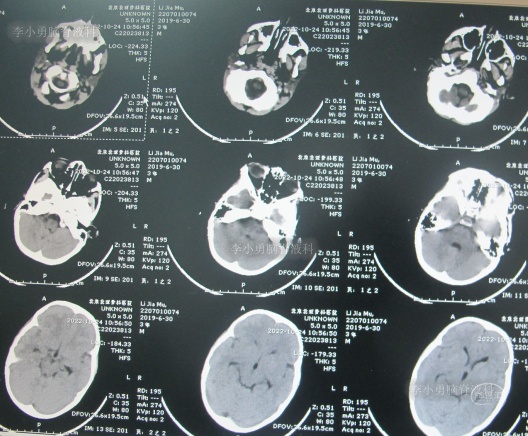

住院治疗7天即2022年5月18日,出现头痛,呕吐,体温再次升高为39.6度,心电图示室性心动过速,室早,考虑“心肌炎”,查头颅核磁(图-1)后并行腰穿见脑脊液呈金黄色,留取脑脊液送常规化验提示诊断为颅内感染,给予抗感染治疗。

图-1:2022年5月18日头颅核磁